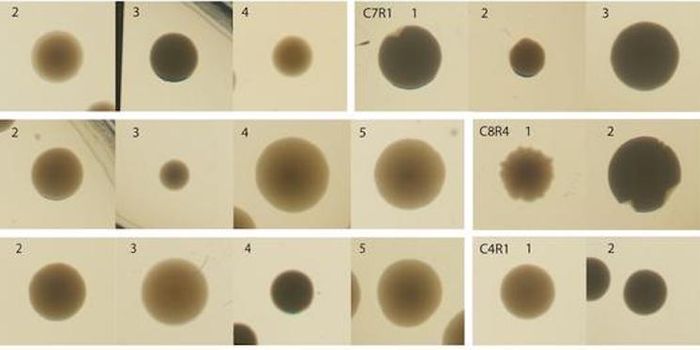

APR 24, 2023Cell & Molecular BiologyPublished by Bindi M. Doshi, PhD on Mar 17, 2023 Organoids are 3D structures made up of cells that replic ...